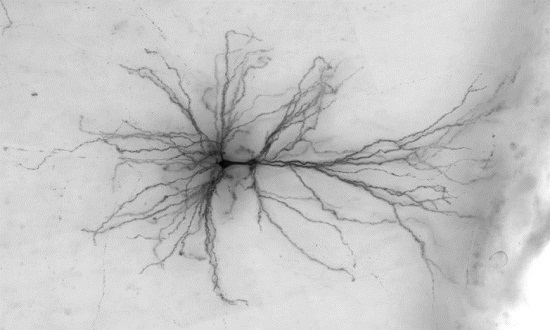

36 farklı hastada gerçekleştirilen beyin ameliyatları sonucu mecburen alınmak zorunda olan yüzlerce sağlıklı beyin hücresi üzerinde yaptıkları çalışmalar üzerine yaptıkları, 3D modellemeler ve gelişmiş bir yazılım sayesinde, sanal ortamda insan hücresiyle tam olarak aynı çalışan bir beyin hücresi modeli yapılabildi. Gönderdikleri elektrik sinyallerini gönderme biçimlerine kadar neredeyse birebir aynı olan bu modeller, insan beyni üzerinde olan çalışmaları hızlandıracağa benziyor.